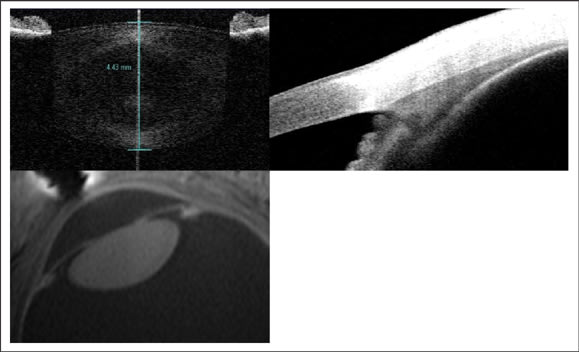

Despite being the most common ocular refractive condition, there is still a limited understanding of the complete process of accommodative loss. In Helmholtz's well-accepted theory of accommodation, the ciliary muscle contracts, causes a reduction in zonular tension and allows the crystalline lens to become more curved and higher powered. Helmholtz's idea that presbyopia is due to age-related sclerosis of the lens is not as well accepted and has been challenged by research that suggests that changes in the ciliary body, zonules and/or arrangement of the structures of the accommodative system result in accommodative decline. Thanks to improvements in technology we now know that all of the accommodative structures change either their structure or function with age (Figure 4).

Figure 4. The crystalline lens, ciliary body and geometry of the accommodative structures change with age. In vivo imaging allows researchers to study changes in the human eye. The top images are of the lens (left) and ciliary body (right) obtained with the Visante anterior segment optical coherence tomographer. The lower image is of the arrangement of the accommodative structures obtained with ultra-high field MRI.

With normal aging there is an increase in brunescence of the lens and a corresponding increase in light scatter, especially at shorter wavelengths. The crystalline lens continues to create new cells and to grow throughout life, increasing in thickness by about 18-to-30 μm/year. The increase in lens size alone has been shown to be related to accommodative function. Lens growth occurs almost entirely in the anterior and posterior cortex, with little change to the lens nucleus. Magnetic resonance imaging studies show that there is little, if any, change to the lens equatorial diameter in adulthood. The equivalent refractive index of the lens decreases with age, which partially offsets the power increase that would occur with a thicker and more curved lens; this is often referred to as the "Lens Paradox."